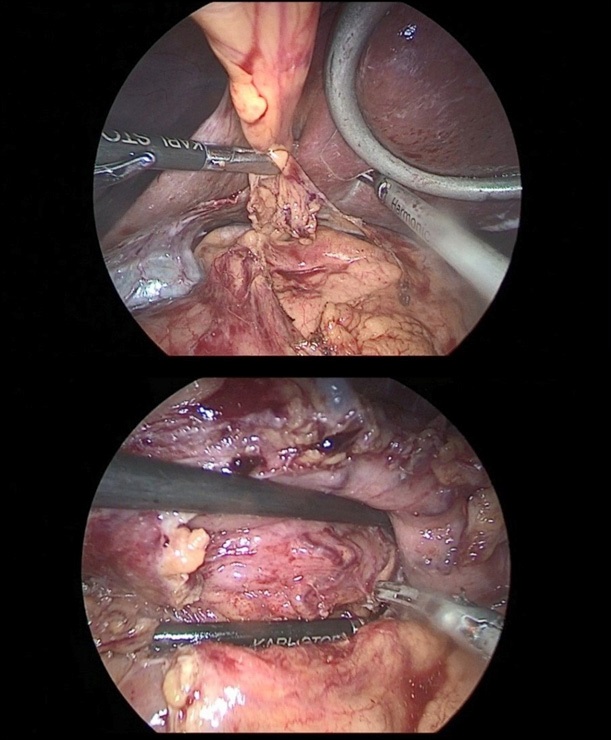

So, after the installation of the optical trocar, and the injection of carbondioxyde to peritoneum, working trocars were introduced and a laparoscopic revision of the abdominal cavity was carried out for the presence of micrometasations of the parietal peritoneum, liver and mesentery of the small and large intestines. After that, was performed the mobilization of the greater curvature of the stomach (Figure 5a,b,c).

The stomach is mobilized to pyloric sphincter. Next, was performed mobilization along the lesser curvature of the stomach (Figure 8). For this, the lesser omentum was resected, lymph node dissection of I, III, V, VII groups of lymph nodes. The left gastric artery was clipped (Figure 6a,b) and transected (Figure 7).

Figure 5a,b,c: Mobilization of the greater curvature of the stomach, the omental bag was opened, there was no infiltration of the serous membrane of the posterior wall of the body and the antrum of the stomach by the tumor. The right gastroepiploic artery was additionally clipped.

Figure 6a,b: Resection of the lesser omentum with removed I, III, V, VII group of lymph nodes.

Figure 7: The left gastric artery was clipped with a Hemo-Lock (X) clip, with additional fixation with tantalum clips.